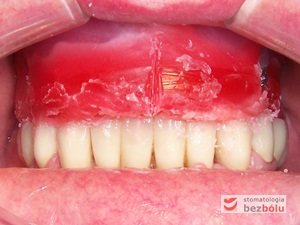

Ostateczny efekt estetyczny wieńczący proces terapeutyczny - odbudowa protetyczna obu łuków zębowych przy zastosowaniu implantów Friadent Ankylos

Ostateczny efekt estetyczny wieńczący proces terapeutyczny – odbudowa protetyczna obu łuków zębowych przy zastosowaniu implantów Friadent Ankylos

Uśmiech pacjenta choć nieśmiały... dla lekarza bezcenny!

Uśmiech pacjenta choć nieśmiały… dla lekarza bezcenny!